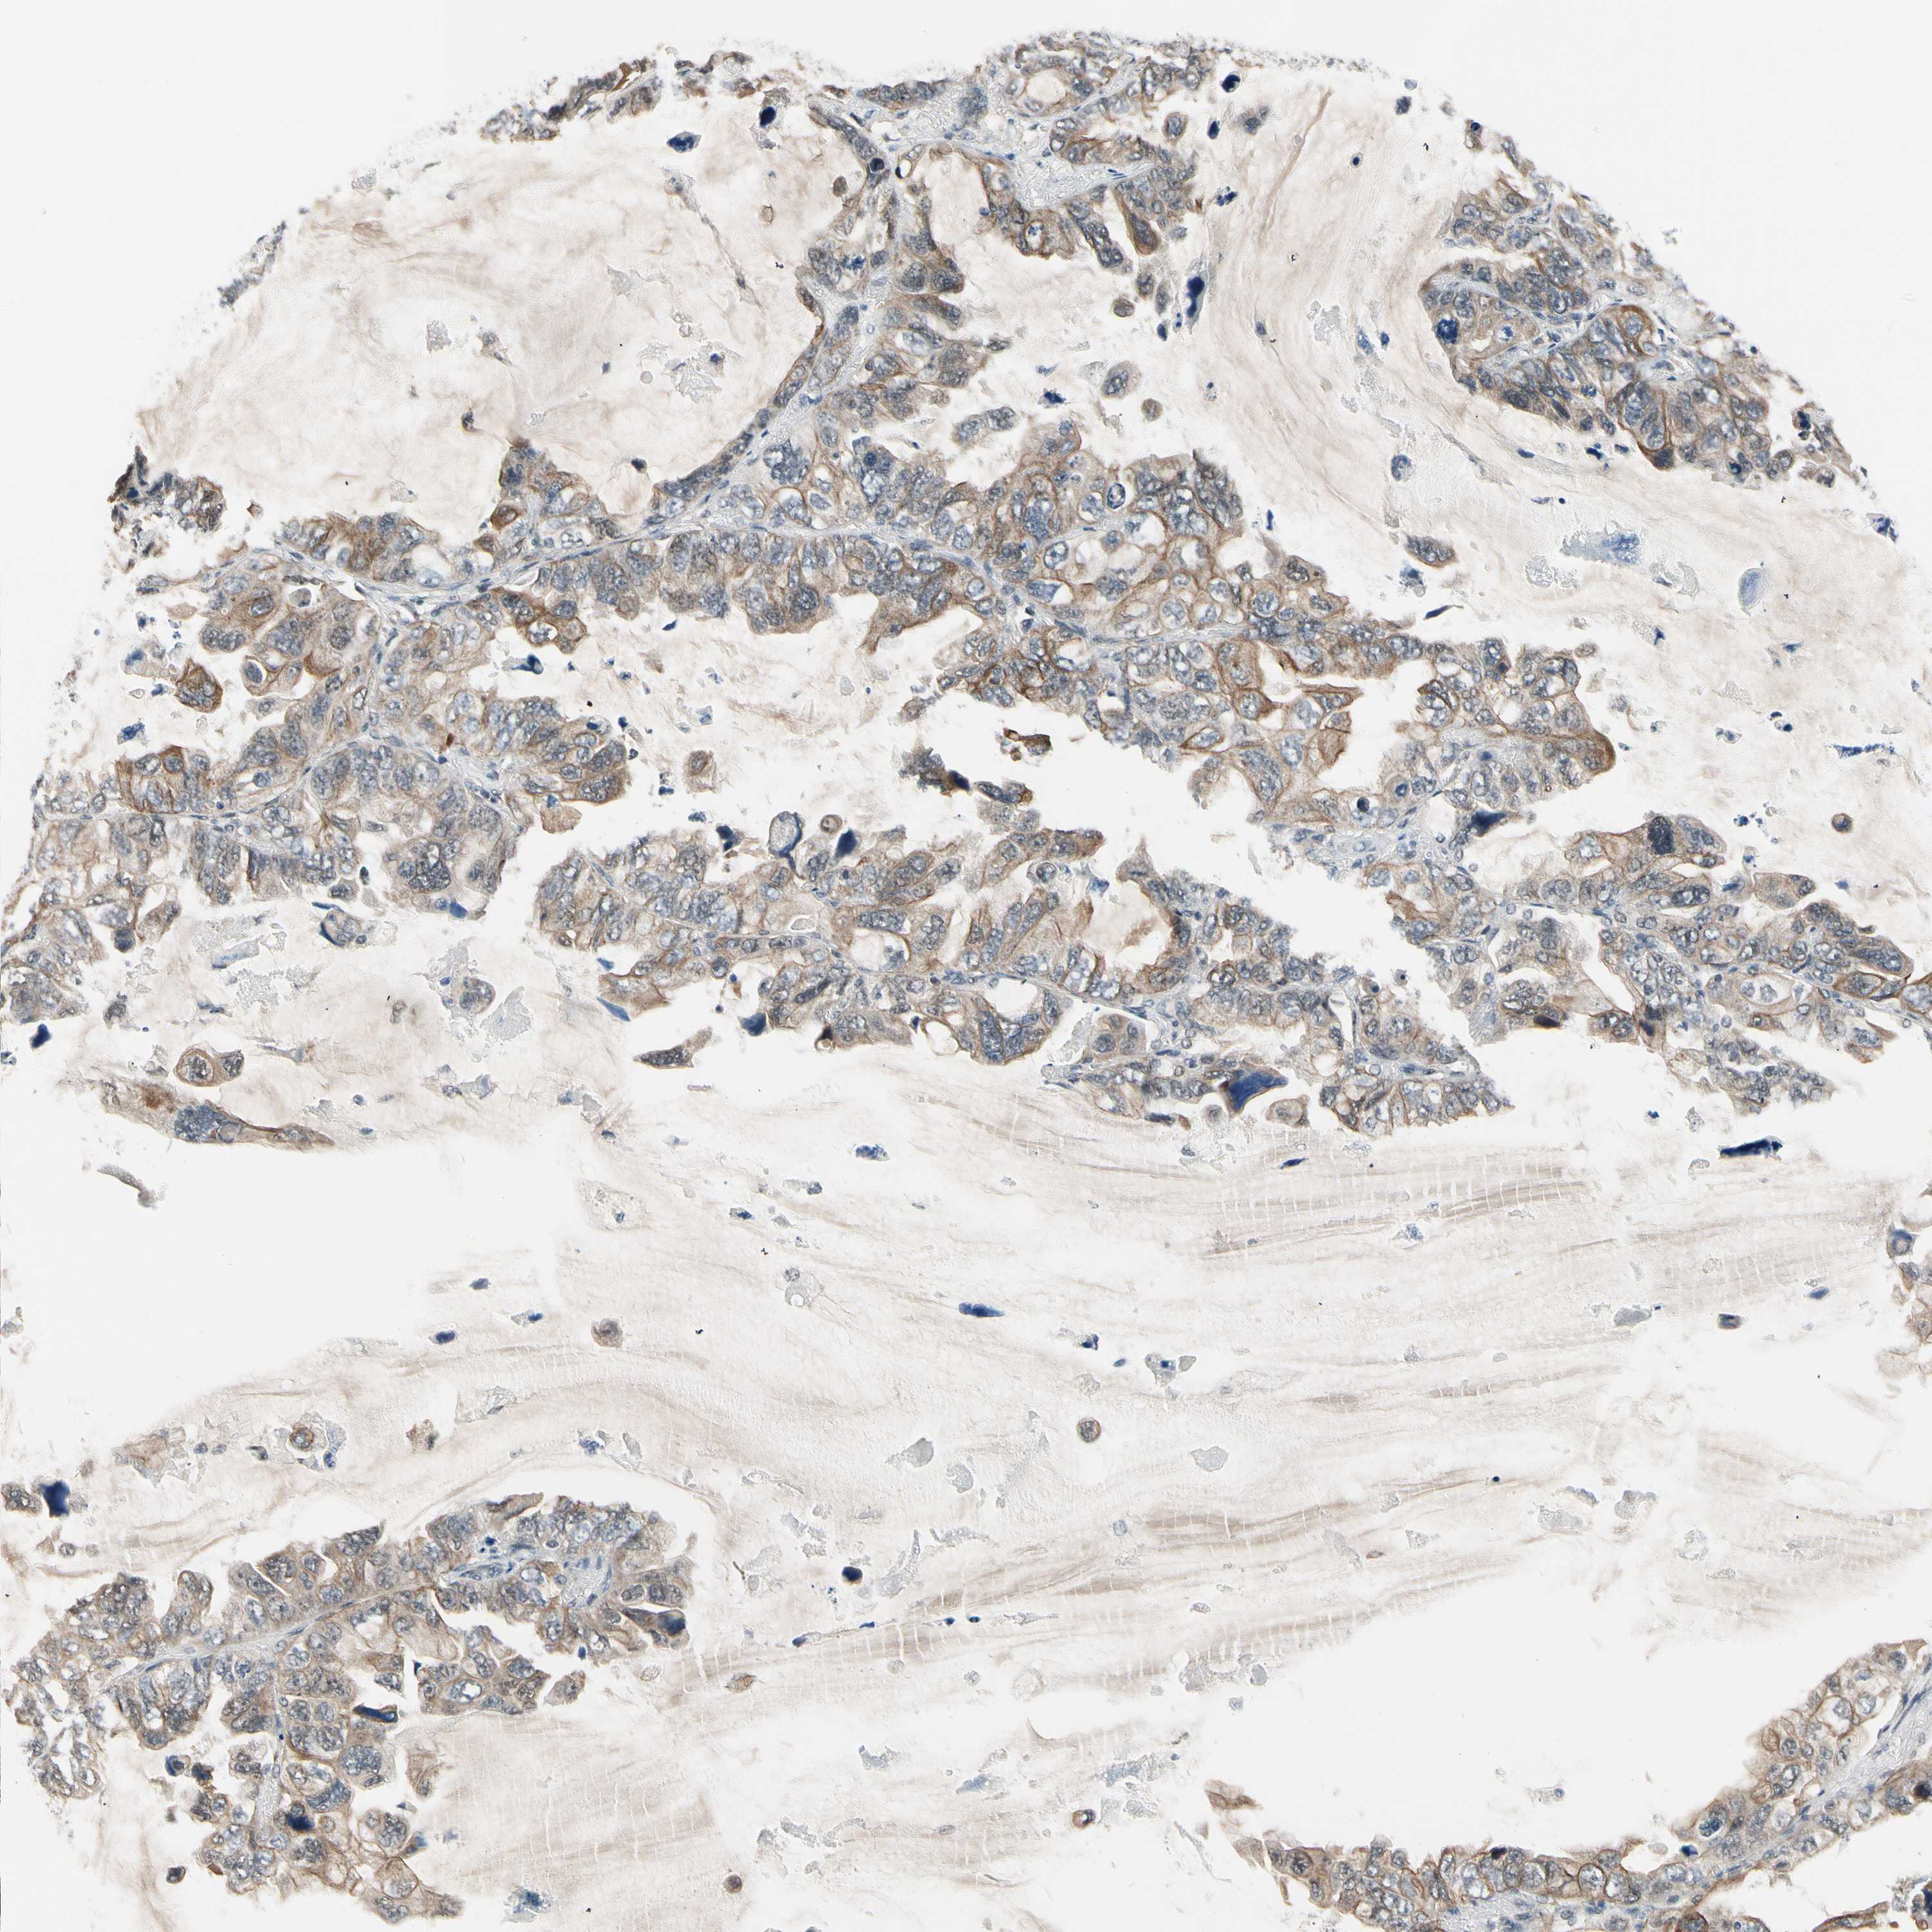

CANCER LUNG CANCER Show tissue menu

LUAD TCGA LUAD VALIDATION LUSC TCGA LUSC VALIDATION PROTEIN LUAD CPTAC PROTEIN LUSC CPTAC PROTEIN EXPRESSION

ANTIBODIES

AND

VALIDATION